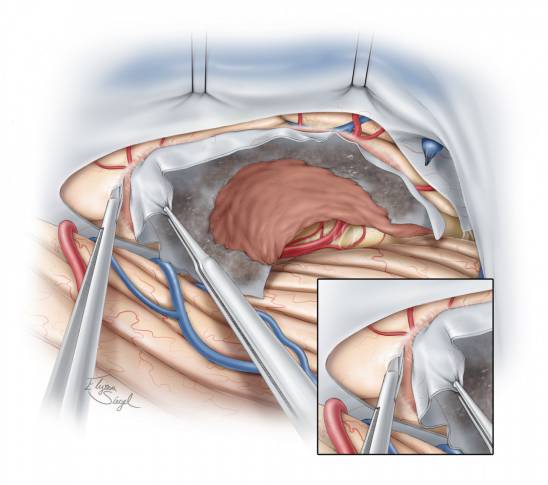

图11. 在切开天幕暴露肿瘤后,可通过吸引器和双极电凝来对质软肿瘤行内减压,而对纤维性质地坚硬的肿瘤则可通过吸引器和CUSA(超声吸引器)配合来进行切除。但在内减压肿瘤过程中不应在视线不及的瘤壁外侧操作。

图12. 在对肿瘤进行足够的内减压后,再分离瘤壁与周围如枕叶底部和颞叶后部等神经血管组织,在这分离过程中注意保护大脑后动脉。

图13. 小块的脑棉垫片用来逐渐垫开肿瘤与瘤周组织。这一操作与处理凸面脑膜瘤类似。经天幕入路本质上是将一个中线区域的天幕脑膜瘤变为凸面脑膜瘤。